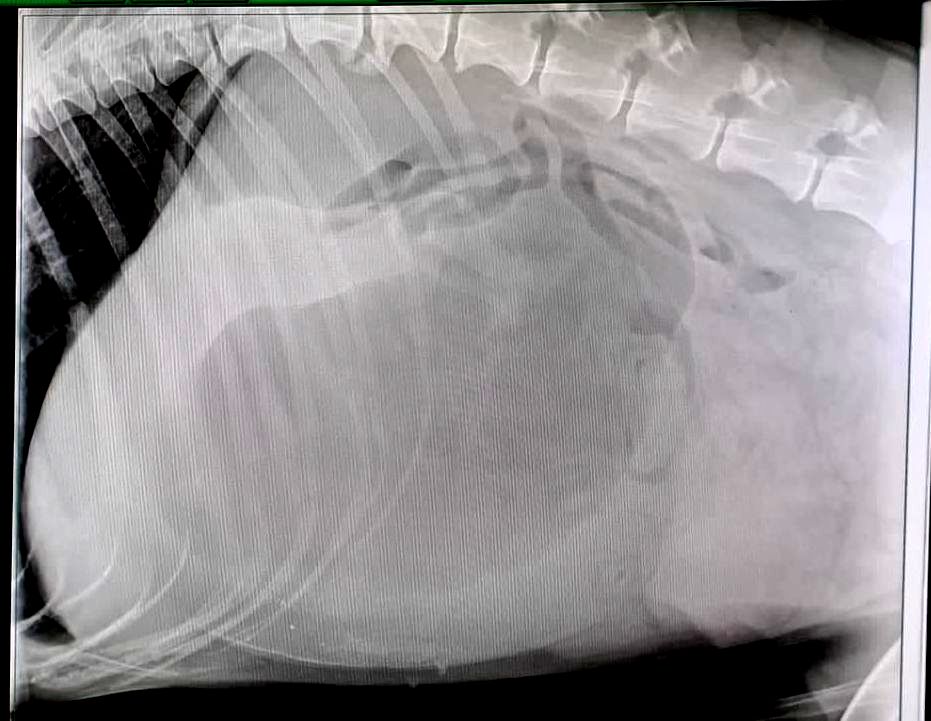

Heute wurde uns ein Hund mit Erbrechen seit gestern und Apathie vorgestellt, auf Nachfrage sagten die Besitzer, dass es dem Hund schon einige Tage nicht gut gehe. Die klinische Untersuchung wies schon in die Richtung, das Röntgenbild bestätigte die Verdachtsdiagnose Magendrehung.